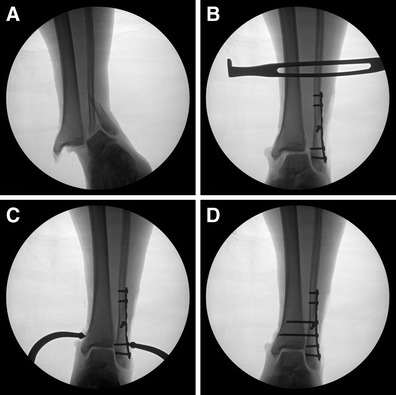

Fig. 3.

Fluoroscopic images illustrating unstable supination external rotation fracture pattern with syndesmotic disruption (a), lateral translation stress after fixation of the fibula fracture (b), syndesmosis reduction technique using a large reduction tenaculum (c), and fixation of the syndesmosis with 3.5-mm screws (d)

While the most common fracture location in syndesmotic injury is the distal third of the fibula (Fig. 3), the fracture level is related to the extent of ligamentous disruption of the syndesmosis. This usually involves rupture of the AITFL and interosseous membrane, with PITFL disruption (or posterior malleolus injury) in severe injuries. Disruption of the syndesmotic ligaments can also result in a fracture at the proximal fibula, or “high fibular fracture,” referred to as a Maisonneuve injury. Maisonneuve fractures generally occur with extensive rupture of the interosseous membrane [9]. These are indicative of severe trauma to the syndesmotic ligaments.

Lower grade (grades I and II) isolated syndesmotic sprains can generally be successfully treated nonsurgically, since they do not result in diastasis and complete ligamentous disruption [32•]. However, these can take up to 3 times longer to heal than inversion ankle sprains. Injuries that occur in conjunction with a fracture and those with clear destabilization of the mortise generally require surgical treatment of the fracture. In these injuries, syndesmosis instability can be assessed intraoperatively in order to determine the need for syndesmosis stabilization (Fig. 3).

Trans-syndesmotic screws

Trans-syndesmotic screws are a highly effective method for achieving stable fixation, allowing the syndesmotic ligaments to heal with appropriate aftercare (Fig. 3). There exists an extensive literature pertaining to the technical attributes of syndesmotic screw materials and configuration. Rates of fixation failure do not appear to be different when stainless steel screws are compared with titanium screws [57]. Larger, 4.5-mm screws provide greater resistance to shear stress than do 3.5-mm screws [58], but cadaver testing suggests that there is no biomechanical advantage based on screw type during pronation external rotation injury [59]. Two syndesmotic screws provide superior stability, as compared with one [45], but biomechanical stability and outcomes are no different when three-cortical is compared with four-cortical screw placement [48, 57, 59, 60]. The position of the foot during insertion of the syndesmotic screw does not impact final ankle range-of-motion or clinical outcome [61, 62].